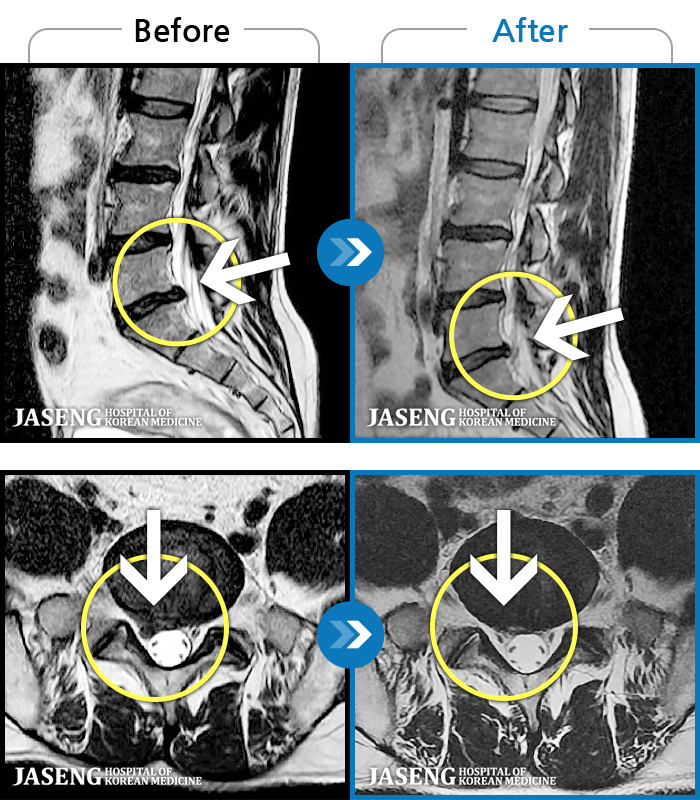

- MRI ġ

MRI ġ

1,299 MRI ũ ʸ Ȯϼ.